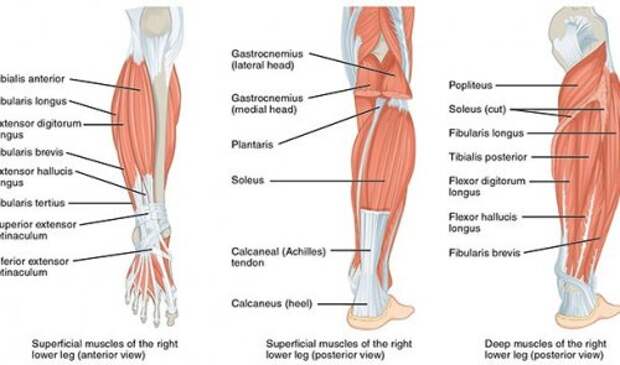

13. В нашем теле существует три типа мышц. Скелетные мышцы соединены со скелетом, помогая нам сознательно двигаться. Сердечная мышца связана с сердцем и неподконтрольна человеку. И, наконец, гладкие мышцы, которые сокращаются непроизвольно, независимо от желания человека, и помогают в таких процессах, как пищеварение или зрение.

16. Учёные из Техасского университета в Остине (University of Texas) нашли способ создания искусственных мышц из рыболовной лески и швейных ниток. Такие мышцы более чем в 100 раз мощнее обычных.